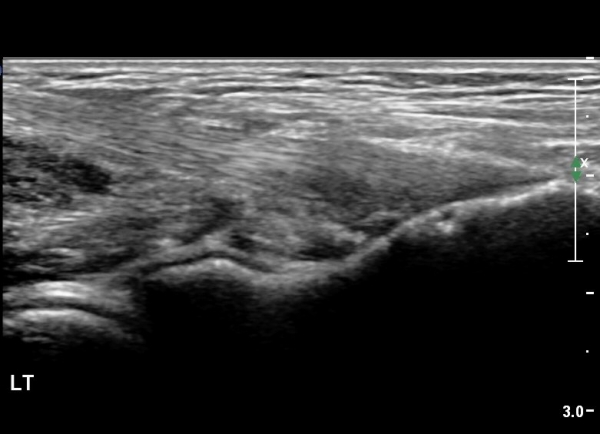

¿ìÃø ÆÈ²ÞÄ¡ ¾ÕÂÊ¿¡¼­ ÀÌµÎ¹Ú±Ù°Ç È¾´Ü¸é°Ë»ç¿¡¼­ À̵ιڱٰǿ¡ ƯÀÌ ¼Ò°ßÀ» º¸ÀÌÁö ¾Ê(±×¸² 1, 2).